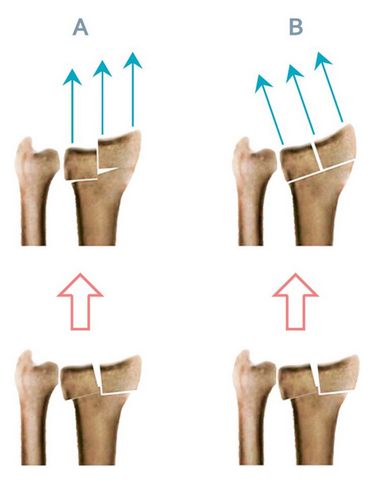

Agee等人先前研究了手掌倾斜恢复极限,他们采用单侧外固定装置进行多平面复位策略。我们试图在术前确定解剖角度,并使用固定角度的EF以避免术中试错,并希望最终确定多平面BEF平面设置的标准。我们假设施加垂直于腕关节的牵引力,而不是平行于桡骨轴的牵引力,可以改善滑脱性,从而减少BEF方法相关的并发症。我们之前的案例系列研究调查了这个问题。根据这一假设,在使用BEF时,牵张力方向的指示调整可以避免平行于关节面施加的剪切力,从而避免桡侧碎片和关节步的移位(图1)。因此,骨折前腕关节倾斜和桡侧倾斜在固定时保持腕关节屈曲和尺侧偏移,可以改善治疗效果。此外,通过调整力的方向,我们可能需要更少的力,减少过度分散的风险。

A - B。外固定定向力的理论修正说明:力平行于半径轴,产生剪切应力,因此关节步骤A,力垂直于桡骨远端关节面,显示更适当的复位B